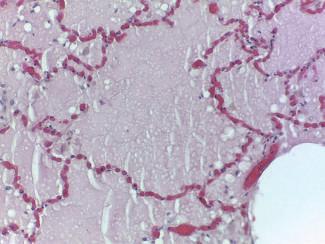

Identificação Genética de Desconhecidos

Palavras-chave: identificação humana; indivíduos não identificados; genética.

Keywords: human identification; unidentified individuals; genetics.

Introdução

A identificação de um indivíduo desconhecido, no âmbito médico-legal e forense, pode ser realizada por diversos mé todos científicos, de entre os quais destacamos a identifi cação genética, que, por regra, só é ordenada ou requerida quando nenhum dos outros métodos disponíveis possibili tou a identificação do indivíduo. Por este motivo e porque as situações que possam envolver um número de vítimas muito alargado são de reduzida ocorrência, em termos quantitativos, as perícias de identificação genética de des conhecidos não se encontram no topo das perícias mais realizadas no âmbito médico-legal e forense. Aliás, na his tória contemporânea de Portugal, o único desastre de mas sa que envolveu um número considerável de vítimas, que tiveram de ser identificadas recorrendo à identificação ge nética, ocorreu em 2017, ficando conhecido na história de Portugal como os incêndios de Pedrógão Grande. Não obs tante a casuística pouco expressiva em termos numéricos, nas primeiras décadas do corrente século XXI, o recurso às perícias de identificação genética tem-se generalizado a ní vel mundial em todas as situações de desastres de massa, chamando a si um papel de extrema importância quer em termos socias, quer em termos humanitários.

Neste capítulo abordamos o âmbito de aplicação da iden tificação genética, bem como os diferentes tipos de amos tras estudados no âmbito destas perícias, os marcadores genéticos utilizados, a valorização estatística dos resulta dos genéticos, as diferentes metodologias laboratoriais dis poníveis e, finalmente, alguns dos casos de identificação genética de especial relevância e interesse histórico.

A abordagem que fazemos à temática da identificação ge nética de desconhecidos tenta utilizar linguagem e nível de complexidade que permita a sua compreensão e, portanto, a sua utilidade, quer para académicos quer para profissio nais, quer sejam das áreas das ciências jurídicas e ciências sociais e humanas, quer sejam das áreas das ciências da vida e ciências médicas.

60.1

Identificação humana

Cada ser humano constitui-se com origem num suporte biológico que se sustenta com uma estrutura psíquica, ao qual as condições histórico-socioculturais em que se de senvolve vincam uma identidade. Este conjunto, que se traduz numa singularidade, numa realidade única, é assim reconhecido na relação entre indivíduos. A singularidade de cada ser humano é-lhe reconhecida pelos demais se res humanos e pela sociedade, não só durante todo o seu período de vida, mas também após a sua morte biológica. Neste alinhamento, o direito português confere a todo o ser humano, por força do princípio da dignidade da pessoa hu mana que inspirou a Constituição da República Portuguesa, o direito à identidade pessoal. Com o nascimento completo e com vida, todos os indivíduos adquirem simultaneamente a personalidade jurídica e inerentemente o direito à identi dade pessoal. Também a Declaração Universal dos Direitos Humanos, no seu artigo 6.º, estabelece que todos os indi víduos têm direito ao reconhecimento em todos os lugares da sua personalidade jurídica, e, portanto, da sua singulari dade e identidade pessoal.

Se é certo que a individualidade psíquica e sociocultural de um indivíduo pode ser moldável ao longo da sua vida, tal não se verifica, salvo situações absolutamente excecio nais, com a identidade genética que é, pois, o suporte da componente biológica de cada ser humano. À semelhança do conceito mais abrangente de identidade pessoal, a identidade genética assenta nas características de cada indiví duo, que se traduzam numa singularidade, numa realidade única e na possibilidade de reconhecimento dessa singula ridade entre diferentes indivíduos.

A identidade de um indivíduo presente aos serviços médico -legais, seja em vida seja em estado de cadáver, na grande maioria dos casos é verificada através daquilo que desig namos por identificação visual e que se baseia na compa ração de cada indivíduo que nos é presente com fotografias de documentos oficiais. No entanto, contrariamente ao que

© PACTOR 905

60

se passa com a maior parte dos indivíduos vivos ou cadá veres humanos frescos, a identificação visual não tem apli cação ou utilidade nos casos de cadáveres em avançado estado de decomposição, maioritariamente cadáveres es queletizados, em remanescentes humanos, em cadáveres recentes que apresentem mutilações, e em particular muti lações faciais, e, nem mesmo, em indivíduos vivos indocu mentados que não tenham, ou afirmem não ter, memória da sua identidade. Nestes casos, de acordo com orientações e consenso internacionais, a identificação individual mé dico-legal é realizada, sempre que possível, recorrendo à lofoscopia ou à informação médico-dentária. Ainda assim, quando nenhum destes métodos permitiu a identificação individual, a genética forense é então chamada a intervir para realização do exame pericial de identificação genética de desconhecido.

Sublinhar que, sendo os métodos de identificação indivi dual todos de natureza comparativa, a lofoscopia, relati vamente à identificação genética, tem, em princípio e na maior parte dos casos, a vantagem de ter quase sempre disponíveis dados para comparação em registos oficiais. É muito reduzido o número de situações em que um indiví duo não tem a sua impressão digital registada em arquivos oficiais. Já no que concerne a registos médico-dentários existem em número muito reduzido se comparados com os registos lofoscópicos oficiais.

Dada a necessidade de comparação, quanto menor e mais específico for o grupo que definimos e ao qual, em prin cípio, pertence o indivíduo ou remanescente humano a identificar, maior será a probabilidade de alcançarmos uma identificação individual positiva. Assim, o contributo prévio da intervenção pericial da antropologia forense, na orien tação da investigação da identidade, pode ser de grande valor. A intervenção pericial da antropologia forense desen volve-se no sentido de apurar o sexo biológico do indivíduo a quem pertencem os remanescentes humanos em estudo, bem como de estimar a sua idade aproximada à altura da morte, a sua estatura e robustez, ancestralidade ou afinida des populacionais, o tempo decorrido post mortem e, even tualmente, algumas informações de especial relevância na individualização dos remanescentes humanos bem como algumas informações no âmbito das causas e circunstân cias da morte. Com o conjunto de informação reunida em resultado da atividade pericial da antropologia forense, o grupo de indivíduos onde se poderá incluir o cadáver ou os remanescentes cadavéricos a identificar será tão reduzido quanto possível, possibilitando, desta forma, maior suces so das intervenções periciais subsequentes, sejam elas da medicina dentária forense sejam elas da genética forense (Amorim, Afonso-Costa, et al., 2011).

A identificação genética de desconhecidos, como já des crito anteriormente, por norma, só é ponderada quando nenhum dos restantes métodos científicos de identificação

médico-legal humana permitiu identificar o cadáver ou os remanescentes cadavéricos. Para este alinhamento con correm essencialmente dois fatores. Por um lado, o facto da identificação genética ser dos métodos periciais mais complexos e mais laboriosos e, por outro lado, o facto da identificação genética ser dos exames periciais mais dis pendiosos em termos de recursos financeiros. Mais ainda, e nesse aspeto não trazendo qualquer diferença ou vanta gem relativamente aos restantes métodos de identificação médico-legal humana, a realização das perícias de identifi cação genética de desconhecidos só é possível se existir um referencial para comparação, seja este uma amostra de referência do suposto indivíduo a identificar colhida an tes da sua morte, sejam objetos pessoais utilizados antes da morte pelo suposto indivíduo a identificar, sejam estes ascendentes diretos, descendentes diretos ou familiares com outros graus de parentesco biológico relativamente ao suposto indivíduo a identificar que concordam de forma livre e informada em ceder amostras biológicas suas para utilização no âmbito da identificação genética de um ca dáver desconhecido a identificar, sendo, aliás, esta última situação o referencial mais frequentemente utilizado, se não mesmo o único possível, no âmbito das perícias de identifi cação genética de desconhecidos realizadas pelos serviços médico-legais.

De há mais de 20 anos a esta parte, a identificação gené tica de desconhecidos, sob responsabilidade dos serviços médico-legais e forenses, concretiza-se através da deter minação do perfil genético do cadáver ou remanescentes cadavéricos a identificar, perfil este que se constitui como o conjunto de informação em determinado número, grupo ou painel de marcadores genéticos, observada no genoma do indivíduo ou remanescentes a identificar.

Existem recomendações científicas internacionais no âm bito das perícias de identificação genética de desconheci dos, relativas a várias matérias, das quais destacaríamos as recomendações relativas às qualificações mínimas dos peritos que realizam as perícias e as recomendações rela tivas aos marcadores genéticos a utilizar na realização de perícias de identificação genética de desconhecidos.

Quanto às qualificações mínimas dos peritos responsáveis por perícias de identificação genética, de acordo com a au toridade internacional competente para a área, a International Society for Forensic Genetics (ISFG), as perícias de identificação genética, aliás como quaisquer outras perícias inseridas no âmbito da genética forense, deverão ser rea lizadas por indivíduos com formação universitária de du ração mínima entre cinco a seis anos, na área da genética humana ou outra área adequada ou afim, e experiência tu telada mínima de três anos, em laboratório e com supervi sor que, também estes, cumpram estas recomendações da ISFG (Morling et al., 2002).

Tratado

Legal 906

de Medicina

Quanto aos marcadores genéticos a utilizar, as recomenda ções internacionais e designadamente as recomendações da autoridade internacional com competência na matéria –European DNA Profiling Group (EDNAP) –, determinam que os marcadores genéticos a utilizar na definição de perfis genéticos no âmbito da identificação humana são os de signados STR (do inglês short tandem repeats), também conhecidos como microssatélites ou como ADN não codi ficante repetitivo em tandem. O elenco dos STR em utiliza ção em cada país, quer em termos quantitativos quer em termos qualitativos, é determinado com base em critérios técnicos e científicos rigorosos e bem definidos que, por seu lado, permitem sempre alguma flexibilidade na decisão final das autoridades políticas competentes, e designada mente no que se refere ao número de STR a utilizar.

60.2

Âmbito de aplicação

A identificação genética de desconhecidos no âmbito mé dico-legal, em regra e como já referido anteriormente, tem sempre lugar quando nenhum outro método científico de identificação humana permite identificar um indivíduo ou re manescentes humanos, podendo, no entanto, por decisão de autoridade judicial ou judiciária ou por decisão do perito médico titular do processo, ser o único método utilizado em determinadas situações em concreto, ainda que, esta segunda alternativa seja de ocorrência excecional.

A identificação genética pode ter por objeto um único indi víduo ou remanescentes humanos com origem num único indivíduo, ou remanescentes humanos com origem em múl tiplos indivíduos. O indivíduo, remanescentes humanos ou

indivíduos a identificar podem ser indivíduos vivos ou ca dáveres, sendo, no caso destes últimos, as situações mais comuns as dos cadáveres esqueletizados (Figura 60.1). Genericamente, no que se refere aos cadáveres presentes para identificação genética de desconhecidos, as situações mais frequentes na rotina pericial dos serviços médico-le gais resultam quer de mortes naturais por doença ou por outros fatores intrínsecos ao indivíduo, quer de mortes vio lentas, nas quais incluímos os suicídios, os homicídios e os acidentes, sejam estes, acidentes rodoviários, incêndios, explosões, derrocadas, naufrágios ou outros.

Quando estamos perante acidentes ou quaisquer fenó menos cuja magnitude e, sobretudo, o número de vítimas, impliquem a necessidade de assistência externa, segundo a Organização Mundial de Saúde (OMS), estamos perante situações que se classificam como desastres de massa. Os principais desastres de massa ocorridos na história da hu manidade têm resultado da ocorrência quer de catástrofes naturais, como erupções vulcânicas, tsunamis, furacões, ciclones, terramotos, inundações, secas extremas, incên dios, de entre outras, quer de acidentes de aviação, quer, ainda, de conflitos bélicos ou de outros conflitos políticos e atos terroristas, dos quais, em regra, o número de vítimas é muito elevado e o número de vítimas a submeter a perícias de identificação genética de desconhecidos pode, também, ser muito elevado.

Para além de indivíduos vivos ou cadáveres para identifica ção genética de desconhecidos no âmbito das situações até aqui elencadas, os serviços médico-legais recebem, ainda, para identificação genética, remanescentes de inter rupções de gravidez (Figura 60.2), fetos ou remanescentes fetais (Figura 60.3), recém-nascidos, bem como amostras biológicas que classificamos como amostras dúbias.

Identificação Genética de Desconhecidos 907 © PACTOR

Fig. 60.1 Corpo esqueletizado, para identificação Fig. 60.2 Remanescentes de interrupção da gravidez, para identificação do pai biológico

Quanto à identificação genética de desconhecidos que tenha lugar em amostras provenientes de remanescentes fetais ou embrionários, sublinharíamos que o artigo 42.º do Código Penal Português prevê que, após interrupção da gravidez ordenada na sequência de crime sexual de viola ção, deve ocorrer identificação genética dos remanescen tes embrionários ou fetais por comparação com a amostra do presumível agressor/pai biológico. Já no caso de na dos-vivos ou mortos em que tenha ocorrido o abandono, a identificação genética tem lugar com vista ao apuramento de quem terá sido a presumível responsável pelo abando no/mãe biológica.

Quanto ao que habitualmente designamos como amostras dúbias, podem ser amostras colhidas no âmbito da realiza ção de análises clínicas ou de outros exames complemen tares de diagnóstico, como exames anátomo-patológicos, e, designadamente, sangue ou fragmentos de tecidos hu manos dos mais diversos órgãos e localizações, e relativa mente às quais não há a certeza do indivíduo, da pessoa a quem pertencem, a quem se referem. As amostras dú bias podem, ainda, ser amostras colhidas não no âmbito do diagnóstico médico, mas no âmbito de exames periciais de toxicologia forense, designadamente sangue colhido em contexto de determinação de alcoolémia ou de determi nação de drogas de abuso, bem como amostras colhidas no âmbito de controlos de dopagem em atletas. Comum a todas as amostras dúbias elencadas é o facto de não exis tir, ou de ter sido levantada suspeição sobre, a verdadei ra identidade do indivíduo a quem pertence determinada amostra e, portanto, a quem ficará associado, a quem será atribuído, determinado diagnóstico médico ou a prática da utilização ilegal de determinada substância ou substâncias.

60.3

Amostras problema estudadas

Se o indivíduo a submeter a perícia de identificação genéti ca for um indivíduo vivo ou um cadáver nas condições que classificamos como cadáver fresco, as amostras biológicas

colhidas para a sua identificação podem ser sangue total em tubo ou em mancha de sangue (Figura 60.4) ou raspado da mucosa oral colhido em zaragatoa.

Fig. 60.4 Fotografia de mancha de sangue (amostra de refe rência), colhida em suporte de papel. Ver a cores